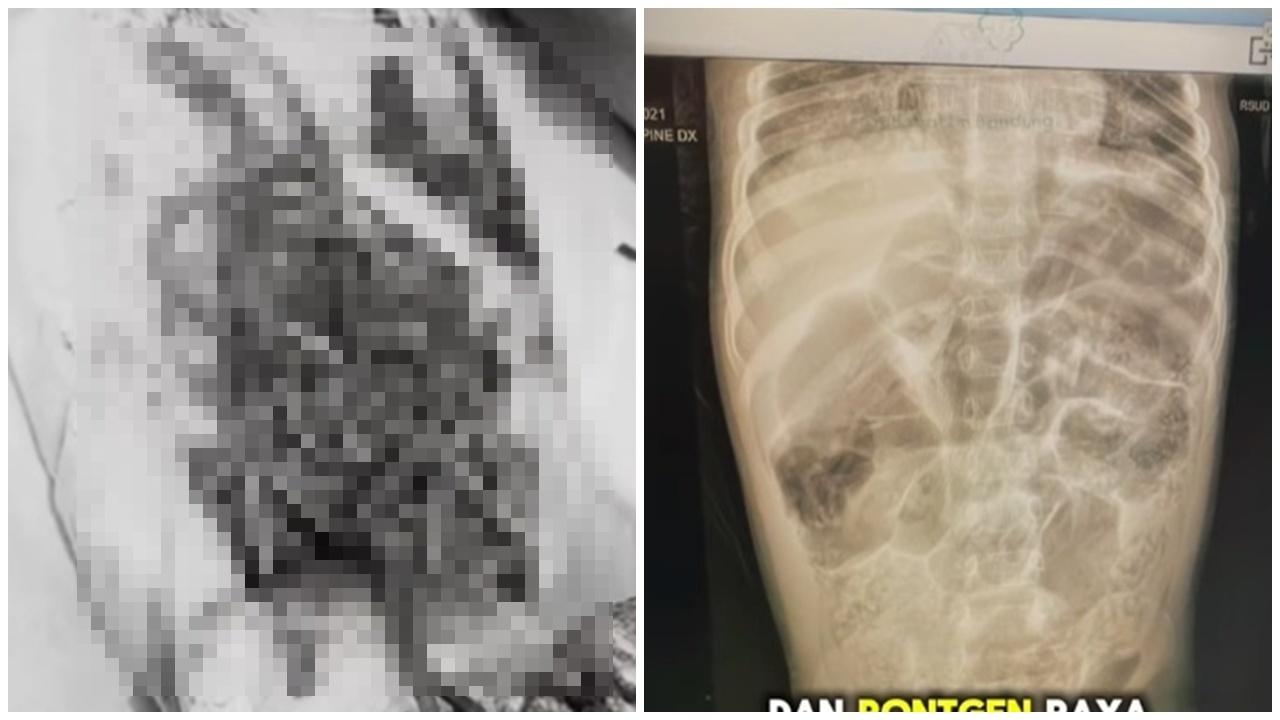

綜合《半城晚報》等內地媒體報道,37歲男子於6月7日和朋友相約到東莞釣魚,下午1點突然感覺嘴巴不受控制地張開,不僅無法說話,就連腦袋也不受控制地向左抽搐點頭。男子說,當時頭腦清醒,但無法用言語表達,所以只能以手心寫字請朋友幫忙叫救護車,但上車前症狀已有所改善。經多家醫院檢查,發現可能是寄生蟲所致,直到他到了廣東三九腦科醫院,神經外二科副主任醫師張旭標才判定他是裂頭絛蟲的幼蟲感染,位置就在大腦掌管語言產生與表達控制的區域。透過影像可以看到蟲體正緩慢向大腦深部移動,因此必須立刻做手術。

男子憶述回到老家回到老家

男子在全麻狀態下開顱,麻醉科醫生將他從麻醉中喚醒,接著遵照指令吐舌、握拳、回答簡單的問題等,藉由即時互動,醫生最終成功捉到長度約10厘米仍在蠕動的裂頭絛蟲幼蟲。術後,恢復狀況良好。男子憶述,小時候喝過生水,回到老家依舊有用井水刷牙的習慣。對此,醫生提醒,裂頭絛蟲幼蟲通常會寄生在青蛙、蛇、田螺等動物體內。如果不慎吃下被其蟲卵污染的生水,或吃了沒煮熟的野生蛙肉、蛇肉,幼蟲就可能進入腸道,並伴隨血液留至全身,如果鑽入大腦就會引發癲癇、肢體無力、語言障礙等症狀,更嚴重會可能危及生命。